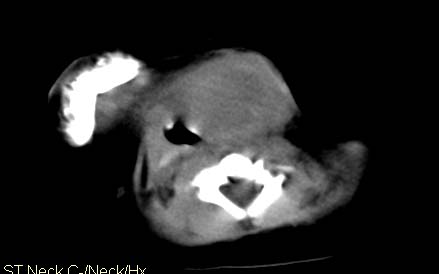

男,26天,发现左侧颈部包块5天,质较硬,患儿不哭不吵,无明显发热,头向右侧歪斜,其父母诉患儿出生时正常,昨天查血象wbc19.4×10的9次方/l,b超考虑来源于甲状腺的恶性肿瘤,我科认为肿块内有低密度区,而且病程发展较快,血象高,考虑炎性病变可能大。患儿年龄太小没做增强。请大家提出高见。

男,26天,发现左侧颈部包块5天,质较硬,患儿不哭不吵,无明显发热,头向右侧歪斜,其父母诉患儿出生时正常,昨天查血象wbc19.4×10的9次方/l,b超考虑来源于甲状腺的恶性肿瘤,我科认为肿块内有低密度区,而且病程发展较快,应该首先排除血肿,其次考虑感染

随访结果:炎症(患儿经过一星期抗炎治疗后颈部包块明显缩小,现已经正常)。